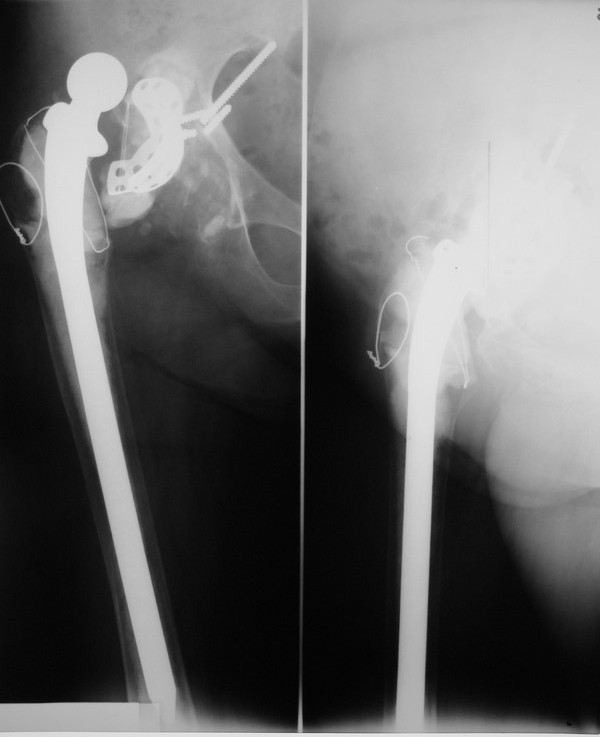

Уважаемые коллеги,в клинику поступила пациентка 51год с нестабильным антипротрузионным кольцом и вывихом эндопротеза.

В течени длительного времени у пациентки ревматойдный полиартрит с приемом преднизолона.В 1994году произведено эндопротезирование правого тазобедренного сустава бесцементным эндопротезом Biotronic.В 2000году по поводу нестабильности эндопротеза проведено ревизионное вмешательство-удаление чашки и ножки, некрэктомия.Установка антипротрузионного кольца, цементной чашки и ревизионной цементной ножки Beznoska.В 2007году выявлена клиникорентгенологическая картина нестабильности кольца.В 2008году пациентка упала, произошел вывих эндопротеза и дислокация кольца с переломом винтов.

Планируем ревизионное вмешательство-удаление кольца, чашки, винтов, пластика верхнего края вертлужной впадины массивным аллотрансплантатом с последующей установкойантипротрузионного кольца типа Burch-Shneider.

PS:у больной в 1998 году установлен цементный эндопротез Beznoska левого тазобедренного сустава и в 2003 году установлен цементный эндопротез De Puy LCS правого коленного сустава.